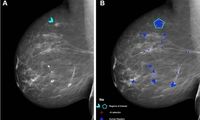

• ماموگرافی یکی از روش های غربالگری و تشخیص سرطان پستان است که به وسیله دستگاه مخصوص تصویربرداری از پستان گرفته می شود و…

• ماموگرافی به عنوان یک روش غربالگری مؤثر، قادر است تومورهای پستان را حتی قبل از اینکه قابل لمس باشند، شناسایی کند. این…